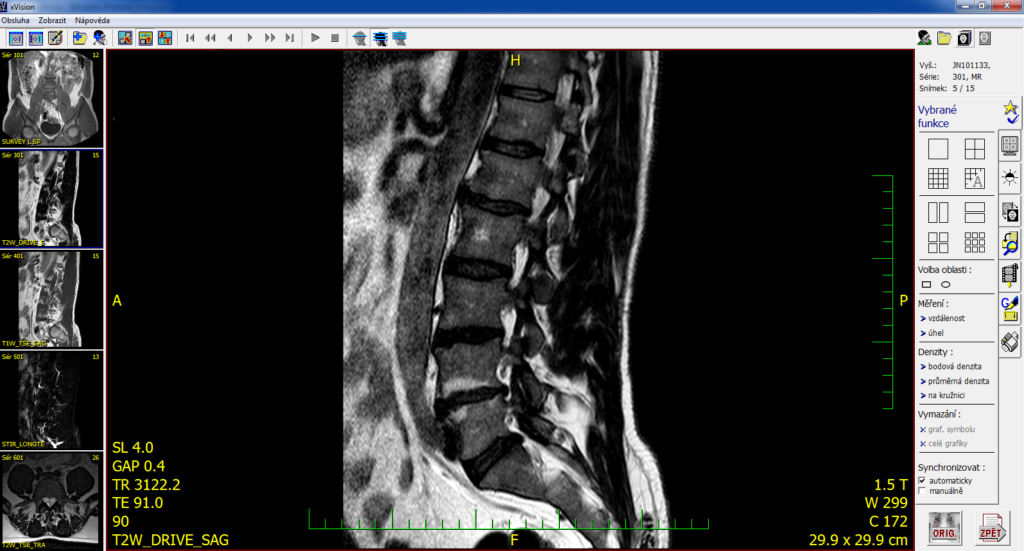

• Degenerativní změny na páteři: Jsou výsledkem nepoměru mezi schopností odolávat tlaku a zátěží, která na páteř působí.